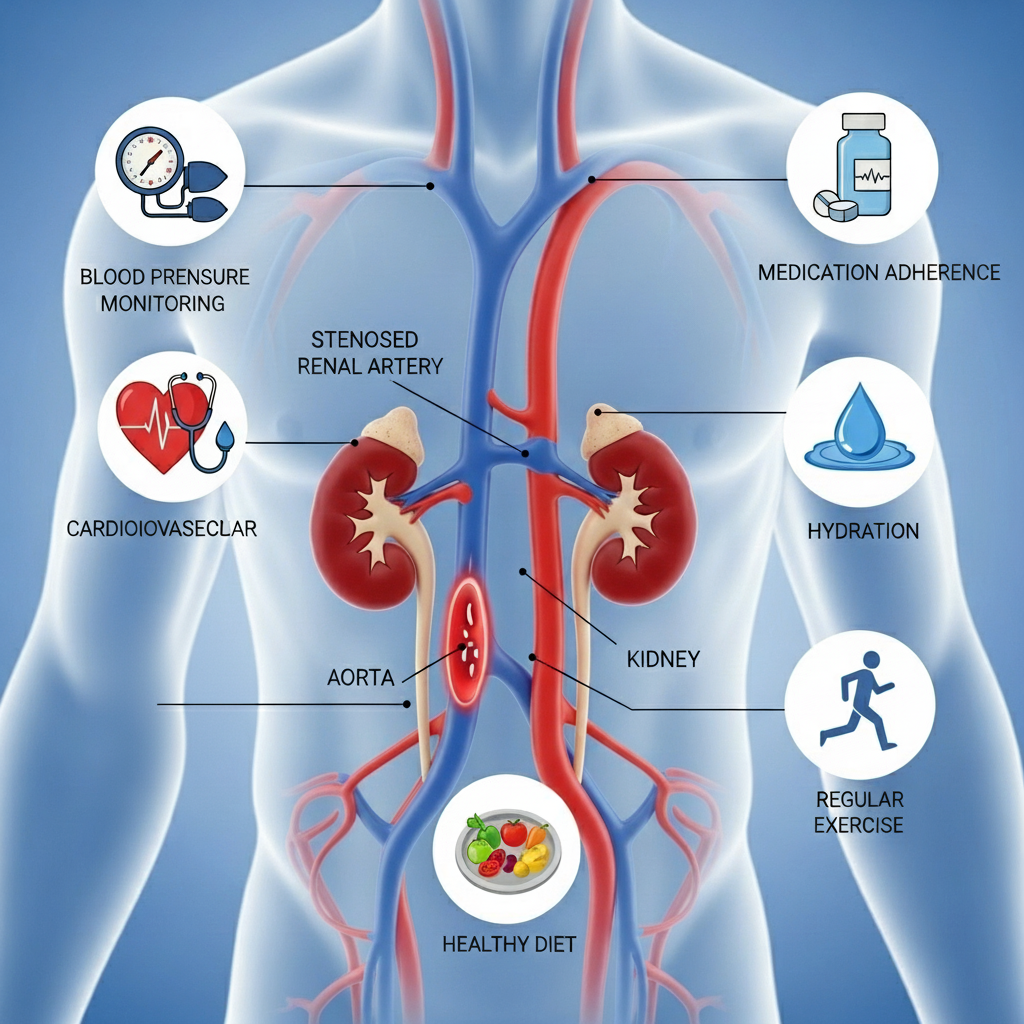

Renal artery stenosis (RAS) is a condition where the arteries that supply blood to your kidneys become narrowed or blocked. This kidney artery narrowing reduces blood flow to the kidneys, leading to high blood pressure and potentially serious complications if left untreated. Understanding this condition is the first step toward effective management and recovery.

Without proper treatment, renal artery stenosis can lead to serious complications:

Increased risk of heart attack, stroke, and other heart-related conditions.

Our commitment to your health extends beyond treatment: